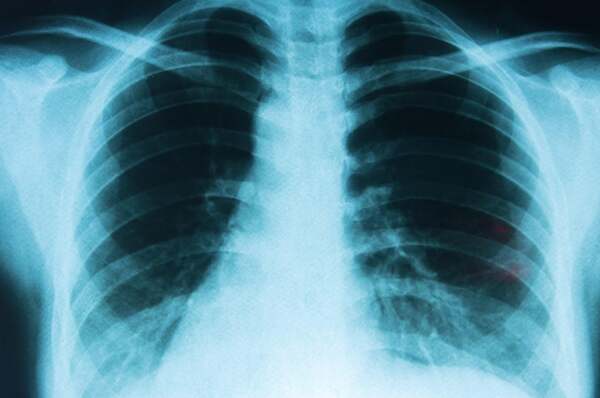

Cáncer de Pulmón: enfermedad prevenible con alta tasa

En el Día de la Lucha contra el Cáncer de Pulmón, se recuerda que es prevenible en un 90% evitando el tabaquismo. ...[Leer más]